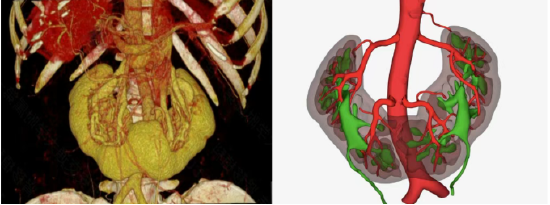

供者马蹄肾CT血管成像(CTA)及三维重建结构图

术前,肾移植团队利用高分辨CTA及三维重建技术,对供体的马蹄肾进行了毫米级的精准评估,清晰勾勒出异常走行的肾动脉、肾静脉及输尿管,特别是明确了相连的肾峡部血供及集合系统情况。本例供者的特点是峡部长度和厚度较大(长7cm,厚2cm),双肾血管复杂(双肾静动脉均为多支,且动脉距离较远),由于国内先前并无此类手术案例参考,国外也鲜有报道,肾移植科结合以往实施公民逝世后捐献马蹄肾手术经验,与相关学科反复模拟论证,制定了详尽的手术方案,为最大化保障供者安全及移植肾功能,最终决定采用腹腔镜下切取结构相对更优的左半侧肾脏,利用遗体捐献血管进行重建后再行肾移植的手术方案。